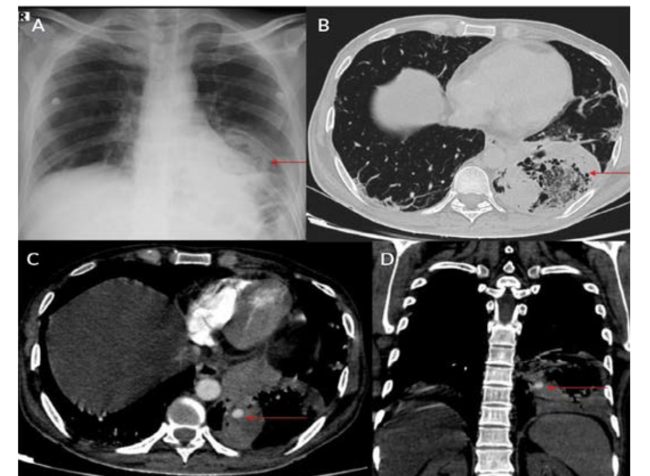

Eight patients were included during this study period; all were men between ages 34 and 61 (Table 1). Positivity to COVID-19 RTPCR test was detected over a period of 2 to 6 months prior to the acute hemorrhage. Six patients presented with massive hemoptysis; 2 presented with severe epistaxis. A contrast-enhanced computed tomography angiography was done in all patients. All 6 patients who presented with massive hemoptysis were detected to have pulmonary arterial pseudoaneurysms with associated cavitary lesions in the lungs (Figure 2). Among the 2 patients who presented with nasal bleed, 1 had a biopsy and culture-proven invasive fungal sinusitis with an internal maxillary artery pseudoaneurysm, probably of mycotic etiology. The second patient also diagnosed with invasive fungal sinusitis had multiple sinonasal debridements outside before presenting with massive epistaxis wherein a diagnosis of internal carotid artery pseudoaneurysm was made, probably secondary to iatrogenic or mycotic etiology. The presence of concomitant COVID-19 infection in these patients predisposed them to impairment of cell-mediated immunity, immune dysregulation, and a decrease in CD4 and CD8 counts, increasing their vulnerability to fungal infections. In 6 patients it was possible to obtain samples for fungal elements through biopsy. Endovascular embolization was performed under local anesthesia in 7 patients, and under general anesthesia in 1 patient. Different embolic agents were used: coils (Figures 3A and 3B), Amplatzer vascular plug (Abbott) (Figures 4A and 4B, Figures 5A and 5B), and glue (Figures 6A and 6B). However, 2 patients underwent lobectomy for extensive parenchymal disease apart from pseudoaneurysm. One patient with pulmonary artery pseudoaneurysm had contrast extravasation into the cavity during the procedure. All patients had cessation of hemorrhage. However, 2 patients required pulmonary lobectomy because of extensive parenchymal disease after embolization for the pseudoaneurysm.

Pulmonary artery pseudoaneurysm is a rare but important entity because of its high risk of life-threatening hemorrhage.2,5,9,10 Peripheral branches of the lower lobe pulmonary artery are most commonly affected.2,5,10 A pseudoaneurysm is different from a true aneurysm because there is no wall except for the hematoma that is surrounding and containing it.6,9,11,12 The etiology of a pulmonary artery pseudoaneurysm is inflammatory erosion secondary to tuberculosis (Rasmussen aneurysm), necrotizing pneumonia, bacterial endocarditis, mucormycosis, or vasculitides (Marfan syndrome, Behçet’s disease, etc.). Other causes include necrotic cavitary lung carcinoma, congenital heart disease, and traumatic injury. Iatrogenic pseudoaneurysm secondary to pulmonary artery catheter placement has also been reported.4-6,9-11 Internal maxillary artery pseudoaneurysm is rare and is more commonly encountered following trauma and iatrogenic injury (Figures 8A and 8B).7,8,13 These patients present with massive or moderate bleeds, which can lead to death in about 50% of cases if left untreated.2,4 The most common artery leading to hemoptysis is the bronchial artery, which constitutes around 80% to 90%.4,5,13 Hemoptysis related to the pulmonary artery constitutes around 10%.10,14 Multidetector computed tomography (MDCT) pulmonary angiography is the modality of choice to diagnose pulmonary artery aneurysms.2,9,10,12 It provides detailed information about the presence, number, size, shape, and origin of pulmonary artery aneurysms.2,9,10 MDCT also allows detailed assessment of the orientation and size of the aneurysmal sac and size of the neck on multiplanar reconstruction.2,10 It also gives an overall idea about the pathology, and the involved lung segment eventually helps in planning the treatment accordingly.4,10,12,14 Digital subtraction angiography has the advantage of allowing endovascular intervention at the time of diagnosis.4,12,14 Ultrasound and magnetic resonance imaging are also used in cases of aneurysms involving neck vasculature.2,14,12